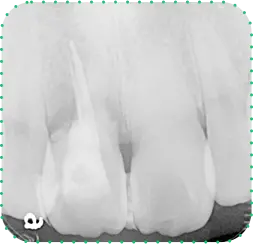

Before

After

主訴

上の前歯が抜けそう

治療期間

6か月

治療費

30万円

治療内容

右上1番を抜歯後に骨と歯茎を増やし、隣の歯の裏側を少量削り、接着性ブリッジにて修復

治療のリスク

咬み合わせによっては、セラミックが欠ける可能性があります。